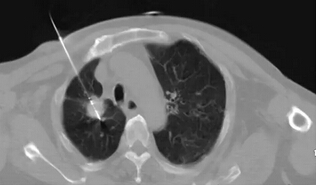

我們?cè)贑T引導(dǎo)下將專用消融細(xì)針插入腫瘤內(nèi)部,CT的引導(dǎo)避免了可能出現(xiàn)的大出血、氣胸等損傷。

僅僅8分鐘就完成了這個(gè)5*8cm的大腫瘤的消融治療,細(xì)心的可以看到腫瘤內(nèi)密度明顯降低了,表明得到了消融?;颊咝g(shù)后恢復(fù)了正常的飲食和活動(dòng)。